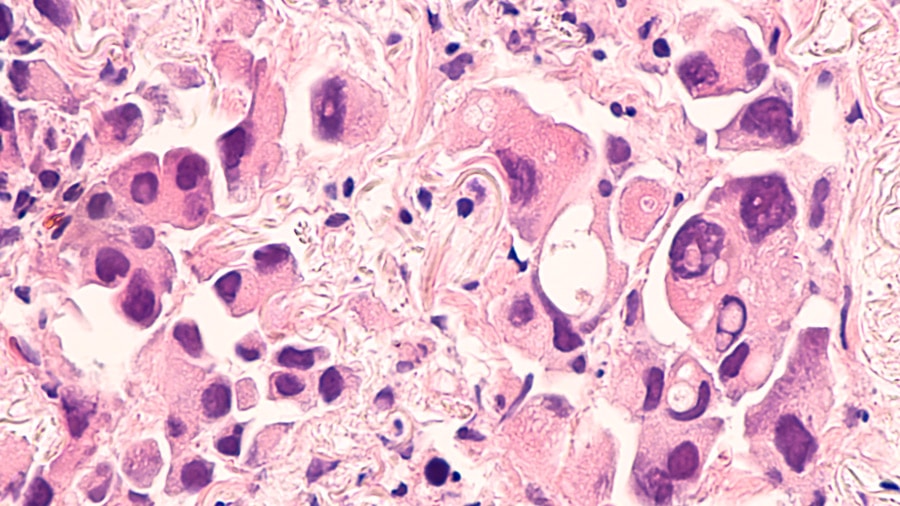

在这项研究中,尤曼科卡博士在20世纪80年代最初从先前未经治疗的非小细胞肺癌患者获得的细胞。为了产生对AFATINIB的抗性,将细胞在含有增加浓度的药物的培养基中生长几个月。然后将这些细胞经受相同的方法重复,但是这次在生长培养基中用罗替尼替尼或口脲酮,以引发对这些药物的抗性。该团队随后使用了各种技术,包括基因组测序,以确定两组耐药性癌细胞中发生的遗传变化。

正如Yamaoka博士和他的同事所希望的那样,他们的研究结果表明,对rociletinib和osimertinib的抗药性确实是独特基因突变的结果。基因扩增——基因拷贝数的增加——在这两种情况下都被观察到表皮生长因子受体和克拉斯,在rociletinib抗细胞中涉及细胞信号传导的另一个基因。扩增和随后的过度表达(其中基因被不恰当地激活,当时表皮生长因子受体突变导致受体蛋白始终处于“开启状态”)在不同类型的癌症中都有发现,这可能是肿瘤变成恶性的原因。

Yamaoka博士也发现了克拉斯奥西替尼耐药细胞的扩增。奥西替尼的耐药程度随药物浓度的增加而增加。重要的是,在一组奥西替尼耐药细胞中,耐药是可逆的;当药物被移除后,克拉斯活动减弱,细胞最终恢复了对奥西替尼的敏感性。在这些细胞中,奥西替尼耐药被发现是由一种特殊的蛋白质复合物引起的。奥西替尼停药两个月后,这种蛋白质复合物分解了。这表明,当患者对奥西替尼产生耐药性时,可以停药两个月;一旦癌症恢复,药物就会再次起作用。Yamaoka博士认为,这将是比持续给药更好的治疗选择表皮生长因子受体TKIS。